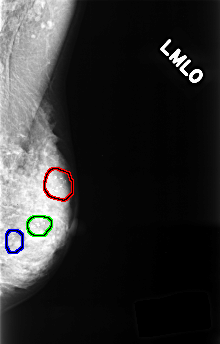

FILE: C_0375_1.LEFT_MLO.OVERLAY

TOTAL_ABNORMALITIES 3

ABNORMALITY 1

LESION_TYPE CALCIFICATION TYPE PLEOMORPHIC DISTRIBUTION CLUSTERED

ASSESSMENT 4

SUBTLETY 5

PATHOLOGY BENIGN

TOTAL_OUTLINES 1

BOUNDARY

ABNORMALITY 2

ABNORMALITY 3